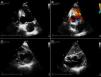

Cardiac magnetic resonance imaging (MRI) confirmed a small pericardial effusion, without hemodynamic compromise, with increased signal intensity in the pericardial space in perfusion sequences, thrombotic material adhering to the walls in early and late enhancement sequences and pericardial late enhancement. These findings confirmed the diagnosis of pseudoaneurysm of the mid and basal segments of the inferior wall, partially filled with thrombotic material (Figure 2 and Video 2).

Cardiac magnetic resonance imaging. Steady-state free precession sequences in 2-chamber long-axis (A) and short-axis (B) view of the left ventricle, revealing pseudoaneurysm of the inferior wall (arrowhead) and a small pericardial effusion; (C and D) early enhancement images showing evidence of thrombus (*) partially filling the pseudoaneurysm; transmural late enhancement involving the basal and mid segments of the inferior septum and the mid segment of the lateral wall. The basal inferior segment of the left ventricular wall is composed of thrombus (*), infarct scar (arrow) and pericardium (arrowhead); (E and F) late enhancement is clearly seen on the pericardial membrane, confirming the diagnosis of pseudoaneurysm.